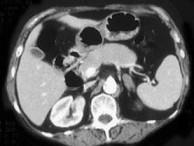

问题 女,42岁,夜尿增多伴高血压,实验室检查:血和尿醛固酮水平增加,请结合图像,选择最佳答案 ( )

选项 A、双侧肾上腺转移瘤 B、双侧肾上腺淋巴瘤 C、双侧肾上腺腺瘤 D、双侧肾上腺未见异常 E、双侧肾上腺增生

答案 E